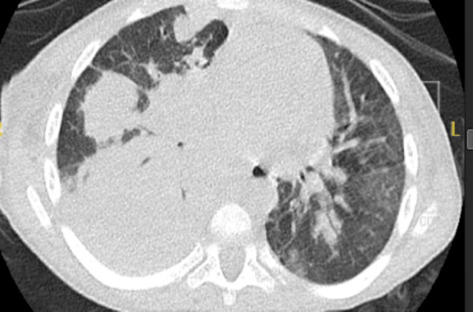

This case illustrates the susceptibility of pediatric patients with chronic lung disease, here, a 3-year-old male with structural airway injury and impaired mucociliary clearance from recurrent aspiration (due to Chiari II malformation and spinal dysgenesis), to life-threatening polymicrobial co-infections, even without classic immunodeficiency. The child was admitted with acute respiratory failure and sepsis; imaging demonstrated necrotizing pneumonia and pneumatoceles; bronchoalveolar lavage confirmed ∗Aspergillus∗ galactomannan positivity and ∗Nocardia∗ species, warranting broad antimicrobial therapy and mechanical ventilation. Diagnosis of invasive aspergillosis and treatment initiation were delayed; despite therapy, he developed multiorgan failure and died. This highlights how chronic lung disease predisposes children to catastrophic fungal-bacterial synergies and reinforces the value of early bronchoscopy for targeted treatment. Advanced disease with structural damage portends poor outcomes, underscoring the need for enhanced surveillance in this high-risk cohort.